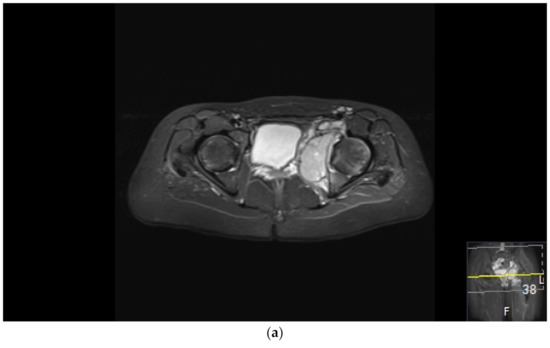

It is well known that ES is a radiosensitive tumor. Initially, surgical treatment was confined to expandable bones, but as surgical techniques evolved, surgical treatment indications extended. Reconstruction with modular and expandable endoprostheses, allografts, endoprosthetic–allograft composites, and vascularized autografts are techniques that have been available for long enough to allow for follow-up over 25 years [88]. These procedures have improved functional outcome and enabled limb sparing surgery [88,89,90,91,92,93,94,95,96]. Recycled autografts and segmental bone transport have additionally improved function, facilitating not only limb-sparing but also joint-sparing surgery (Figure 1) [96,97,98]. Computer navigation, intraoperative CTs, and three-dimensional-printed implants are new tools, especially useful in pelvic surgery, which have further improved accuracy in tumor resection and optimized reconstruction [99,100,101,102,103]. Despite advancements in surgical treatment, complications such as post-operative infection, endoprosthetic loosening, and bone healing difficulties are common in this young and active patient group (Figure 2) [104,105].

Figure 2.

Surgical failure of biological reconstruction after major pelvic surgery, salvaged with endoprosthesis. (a,b) A previously healthy 15-year old girl with 1-year history of left-sided groin pain. MRI of the pelvis (T1 TIRM coronal (a) and axial (b) images) showing a bone tumor involving the left superior ramus of the pubic bone and the periacetabular region of the iliac bone. There is a soft tissue component engaging the obturator internus-externus and adductor muscle. Staging procedures did not show any evidence of metastatic disease. Fine-needle aspiration showed a monotonous small round blue-cell tumor most likely representing Ewing sarcoma. FISH analysis showed an EWSR1-Fli1 fusion transcript confirming the Ewing sarcoma diagnosis. (c,d) After induction chemotherapy with VIDE (vincristine, ifosfamide, doxorubicin, and etoposide), the soft tissue component, as well as the intraosseous extension of the tumor, was significantly reduced, as shown on the coronal (c) and axial (d) T2 TSE FS MRI images. (e) The patient underwent a P2/P3 internal hemipelvectomy, extra-corporeal irradiation with 55 Grey and re-implantation of the autograft. (f,g) One year after primary surgery, the autograft collapsed (f), requiring salvage reconstruction with the Mutars Lumic Cup (g). A year later, the patient is functioning well and remains free of disease.